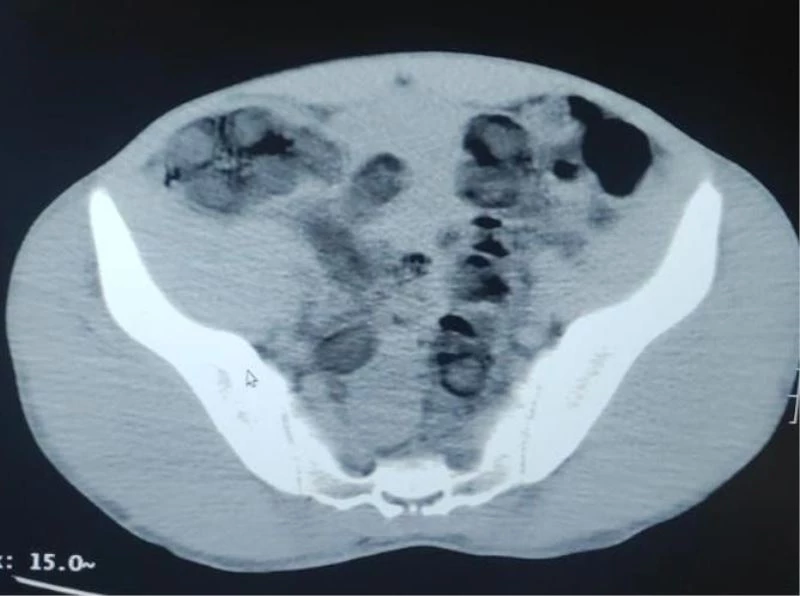

Bitlis’te 2 şüpheli şahsın midesinden 176 kapsül içerisinde 1 kilo 96 gram eroin maddesi çıktı.

Bitlis Valiliğinden yapılan açıklamada, "Bitlis İl Jandarma Komutanlığı unsurlarınca yapılan istihbari çalışmalar neticesinde, Güroymak ilçesi Günkırı mevkiinde icra edilen yol kontrol faaliyetinde, Van-İstanbul seferini yapan bir yolcu otobüsünde iki şüphelinin vücutlarında uyuşturucu madde taşıdıkları bilgisi alınmıştır. Şüphelilerin çekilen tomografi ve röntgen görüntülerinde mide ve bağırsaklarında yabancı cisim olduğu tespit edilmiştir. Yapılan operasyonla her iki şüphelinin midesinden toplam 176 adet kapsül içerisinde 1 kilo 96 gram eroin maddesi ele geçirilmiş, şüpheli 2 şahıs gözaltına alınmıştır. Gözaltına alınan 2 şüpheli adli işlemlerinin tamamlanmasına müteakip 22/23 Şubat günlerinde adli makamlara sevk edilmelerine müteakip tutuklanarak Bitlis kapalı cezaevine teslim edilmiştir. Yarınlarımızın teminatı olan çocuklarımızı ve gençlerimizi uyuşturucudan korumak maksadıyla, uyuşturucu madde türevlerinin ticaretini yapan veya sosyal medya aracılığı ile alenen özendiren şahıslarla, yılmadan ve yorulmadan etkin mücadeleye bölge halkının da desteği ile kararlılıkla devam edilmektedir" denildi.